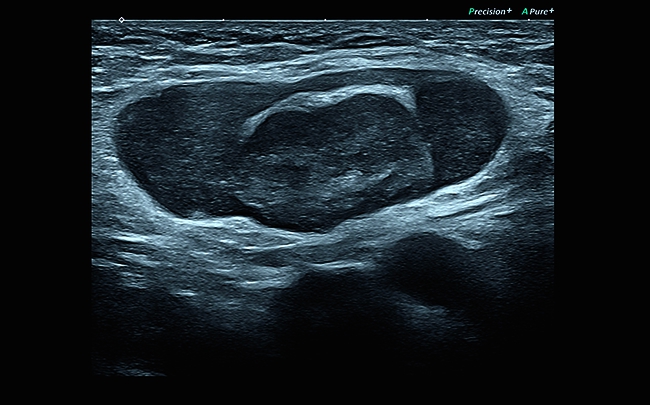

• Технология Precision Imaging

• Технология ApliPure+: многолучевое сканирование в реальном времени для повышения качества изображения

• Технология MicroPure для обнаружения небольших концентраций солей кальция

Многолучевое сканирование

Чем больше лучей, тем лучше! Ультразвуковые лучи подаются под различными углами, после чего происходит суммирование всего объема полученных данных. Вы получите значительное повышение четкости изображения, которое приближается по качеству к картинке томографа.